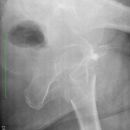

Cam FAI mit herniation pit